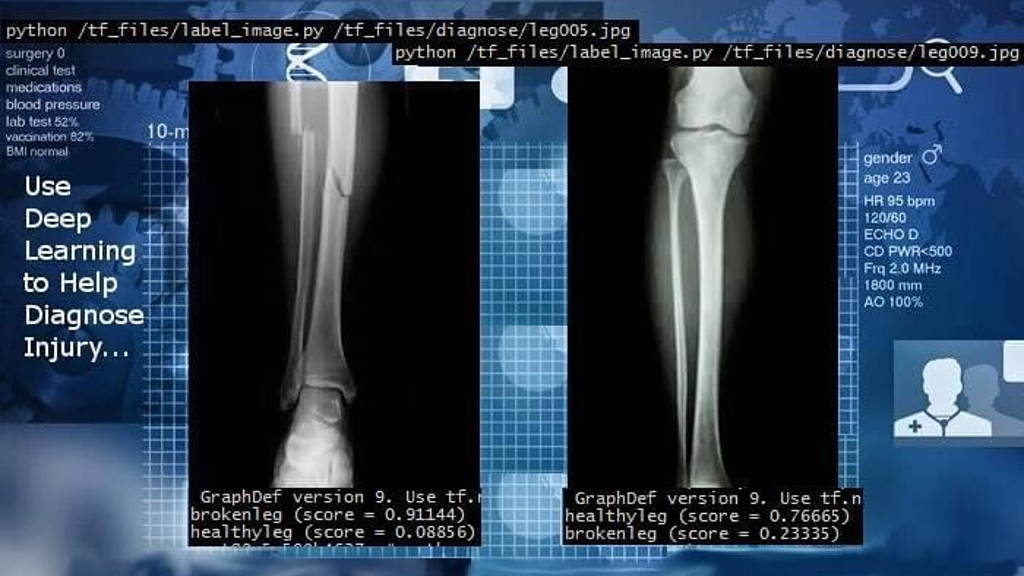

Het foutpercentage bij patroon– en beeldherkenning door kunstmatig intelligente diagnostische systemen is de laatste twee jaar gedaald tot circa 2%. Dan rijst de vraag of AI het niet beter doet dan de dokter bij het interpreteren van röntgen/ en scanbeelden of bloeduitslagen. Met nadruk op beter en niet op slimmer!

Betere c.q. nauwkeurigere diagnostiek spaart op onnodige behandelingen met risico’s, gezondheidsschade, verlies van  levens en oplopende kosten. Bij het vaststellen van kanker (o.a. long, huid, borst. bot en buik), tuberculose en bloedbeelden heeft AI-beeldherkenning in de praktijk zijn grote nut al bewezen. Waar menselijke ogen naar afwijkingen kunnen kijken kunnen neurale AI-netwerken met deep learning dat nu ook of zelfs beter. Zelfs de kleinste en potentieel mogelijke afwijkingen ontgaan het AI-algoritme met deep learning-faciliteiten niet. Het lijkt in feite al een kunstfout om deze dan ook niet in te gaan zetten. De medische wereld reageert vaak echter (te) traag op innovaties. 10-15 jaar was in het verleden normaal.